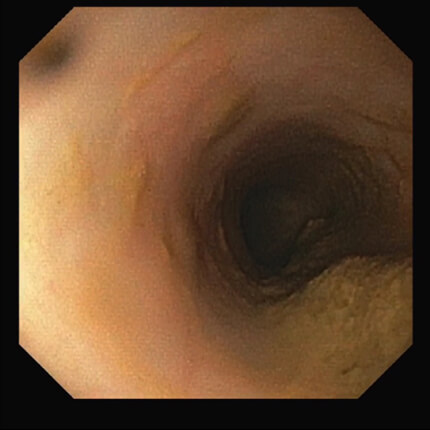

【十二指腸】